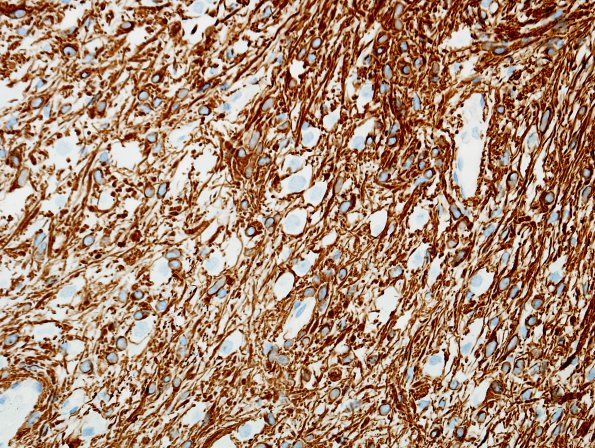

21D3 Ganglioglioma (Case 21) GFAP 3

More confluent glial areas consist of sheets of spindled elements (GFAP IHC)